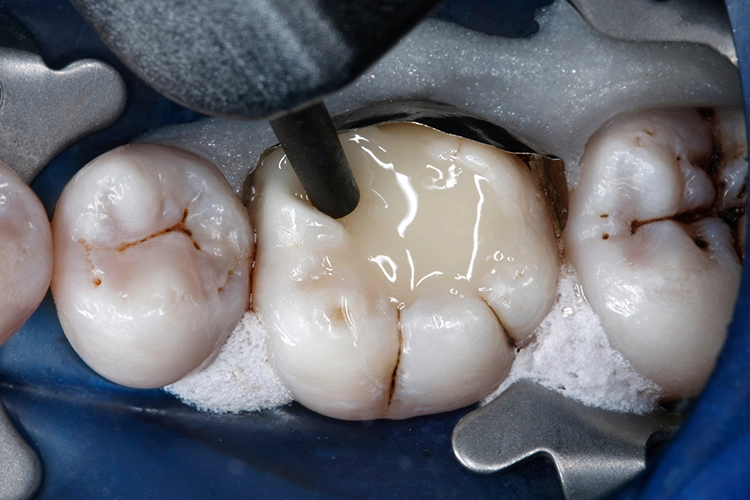

Ein 38-jähriger Patient erschien in unserer Sprechstunde mit einem frakturierten mesiolingualen Höcker neben einer okklusalen Amalgamfüllung am unteren rechten 1. Molaren (Zahn 46). Der Vorfall hatte sich bereits vor einer Woche ereignet, der Zahn war noch am selben Tag im zahnärztlichen Notdienst provisorisch mit einer Glasionomerzementfüllung versorgt worden (Abb. 1). Der Defekt erstreckte sich bis auf Höhe der marginalen Gingiva (Abb. 2).